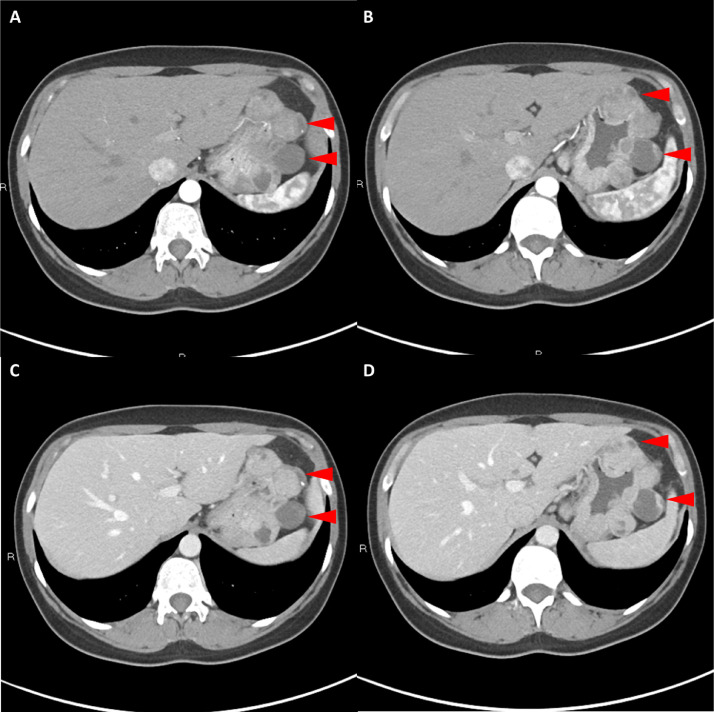

胸部、腹部和骨盆的對(duì)比增強(qiáng)動(dòng)脈和靜脈期 CT 顯示多個(gè)圓形、主要是血管豐富的異質(zhì)腫塊,具有囊性和實(shí)性成分,起源于胃底和胃體(圖 2-4)。 病變部分呈外生結(jié)構(gòu),被認(rèn)為位于粘膜下層。 在頸部多發(fā)同步性副神經(jīng)節(jié)瘤的情況下,賊初的鑒別診斷包括多發(fā)性副神經(jīng)節(jié)瘤、多發(fā)性 GIST 以及轉(zhuǎn)移性疾病。

Fig. 2

圖 2:多發(fā)胃腸道間質(zhì)瘤的軸位 CT 圖像。 (A 和 B)軸位動(dòng)脈相增強(qiáng) CT 圖像和(C 和 D)軸位靜脈相增強(qiáng) CT 圖像顯示多個(gè)圓形、不均勻、增強(qiáng)的腫塊,具有實(shí)性和囊性成分。 腫塊位于粘膜下,結(jié)構(gòu)呈外生。